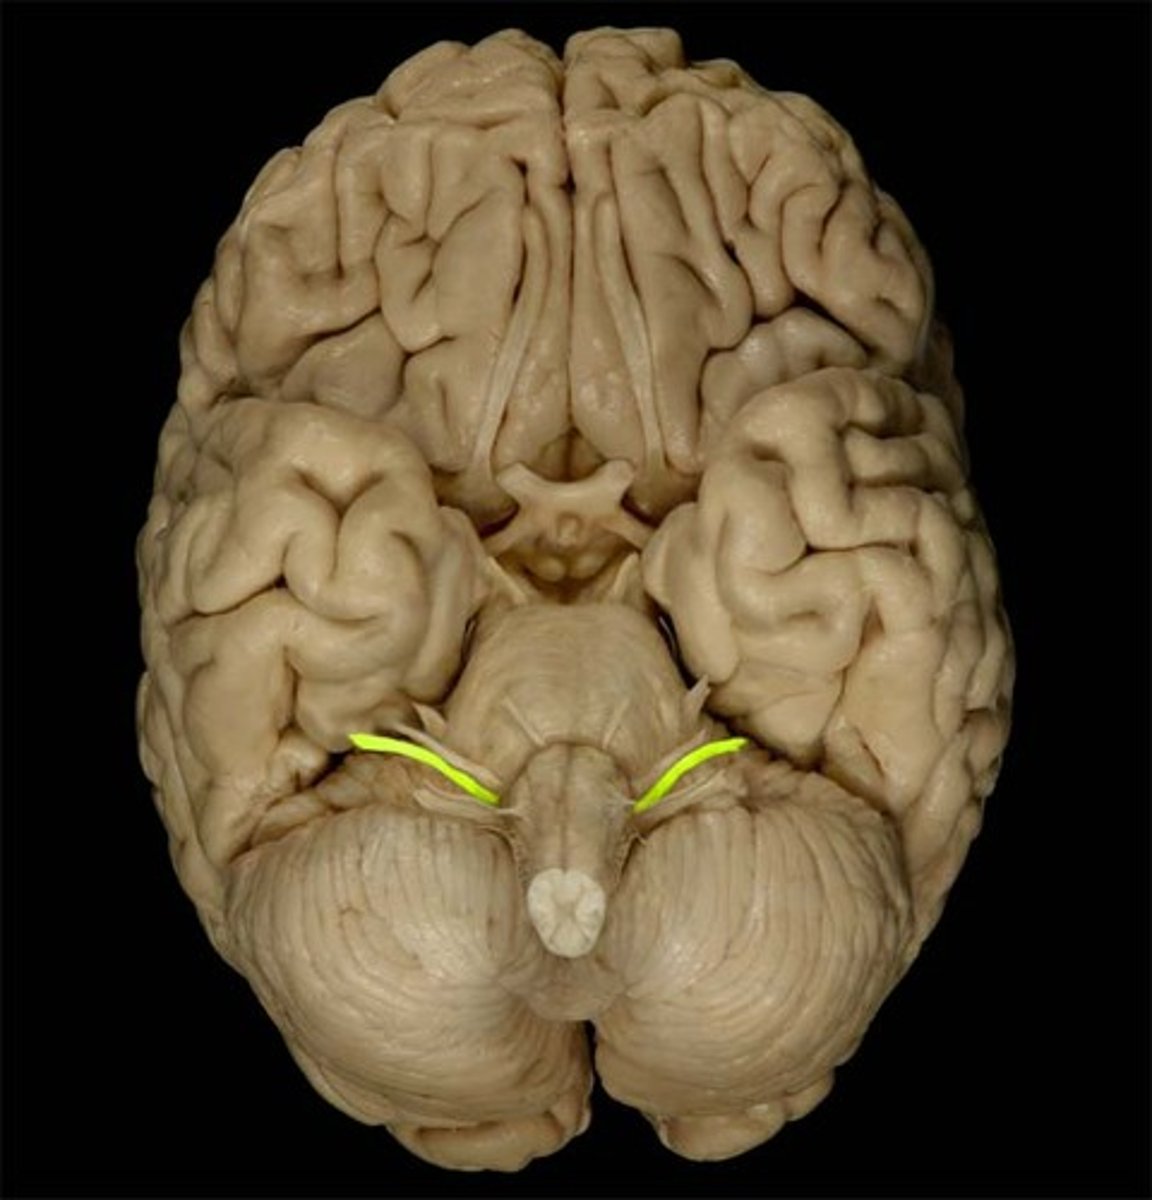

Superior Dorsal View of brain

Gyri

Sulci

Longitudinal Cerebral Fissure

Frontal Lobe

Parietal Lobe

Occipital Lobe

Central Sulcus

Lateral Sulcus

Somatomotor Area

Somatosensory Area

Cerebellum

Olfactory Bulb

Optic Chiasm

Mammillary Bodies

Pons

Medulla Oblongata